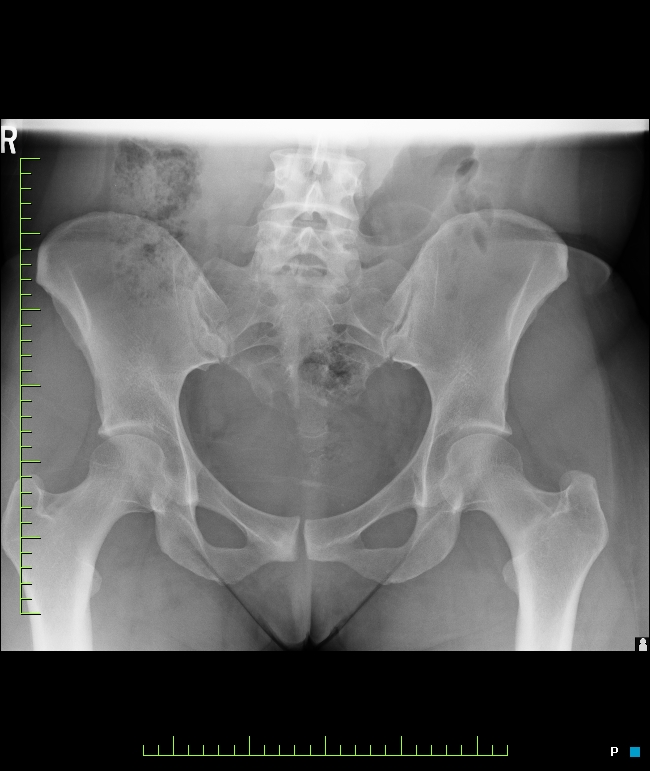

R hip pain for six weeks

Pt is a 32 y/o runner with history of R hip stress fx as a teenager.

R sacral stress fx